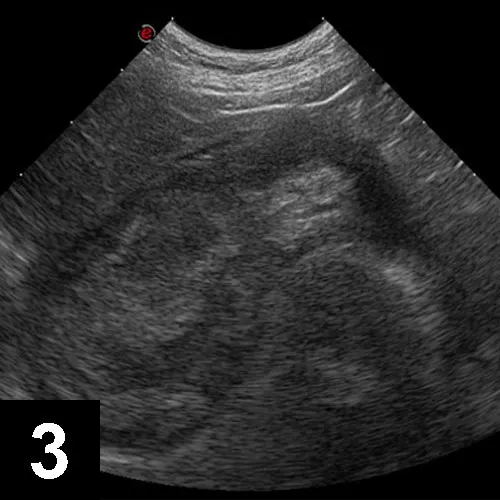

Figure 1C

Ultrasonographic appearance of a gallbladder mucocele showing a finely striated bile pattern in the gallbladder periphery and poorly echogenic bile centrally.